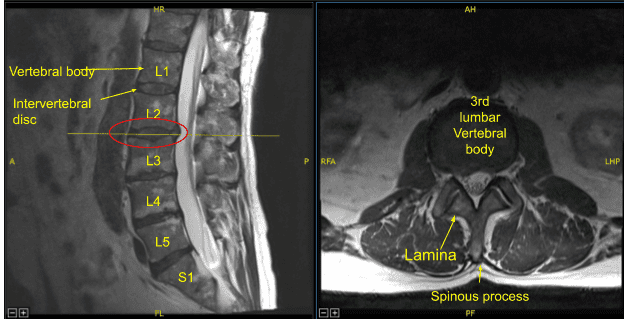

Conservative treatment in the form of physical therapy and medications were tried. No improvement after conservative treatment, an MRI was performed. The MRI showed an extruded disc in the right L2-3. The patient tried an epidural injection which gave temporary relief. Finding no permanent relief, the patient opted for surgical management. The patient understood and signed an informed consent.

Diffuse disc bulge and superimposed right paracentral disc herniation